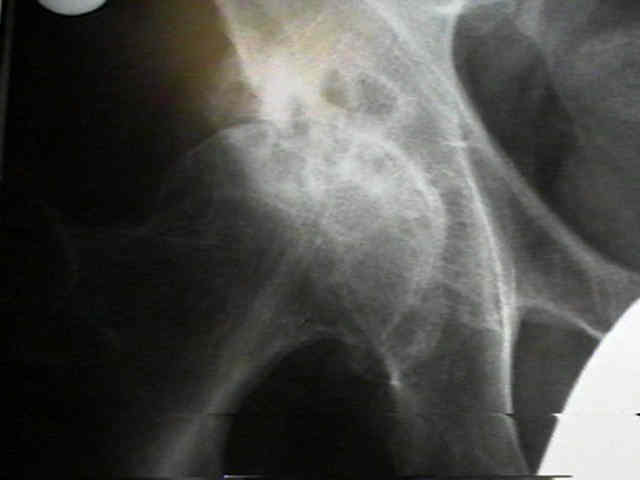

Hip Osteoarthritis

clinical features

Hip Osteoarthritis 2

• pain on wt-bearing felt in the groin, buttock, or medial thigh;

• trendelenburg gait will decrease mechanical stress on joint and thereby lessen pain (see forces acting on hip joint);

• pain during sleep results from loss of protective function of muscular splinting;

• in some cases, a patient w/ OA of the hip will experience acute hip pain which often correlates w/rupture of subcondral cyst into the joint;